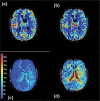

Moyamoya disease is characterized by a chronic stenoocclusive vasculopathy affecting the terminal internal carotid arteries. The clinical presentation and outcome of moyamoya disease remain varied based on angiographic studies alone, and much work has been done to study cerebral hemodynamics in this group of patients. The ability to measure cerebral blood flow (CBF) accurately continues to improve with time, and with it a better understanding of the pathophysiological mechanisms in patients with moyamoya disease. The main imaging techniques used to evaluate cerebral hemodynamics include PET, SPECT, xenon-enhanced CT, dynamic perfusion CT, MR imaging with dynamic susceptibility contrast and with arterial spin labeling, and Doppler ultrasonography. More invasive techniques include intraoperative ultrasonography. The authors review the current knowledge of CBF in this group of patients and the role each main quantitative method has played in evaluating them, both in the disease state and after surgical intervention.